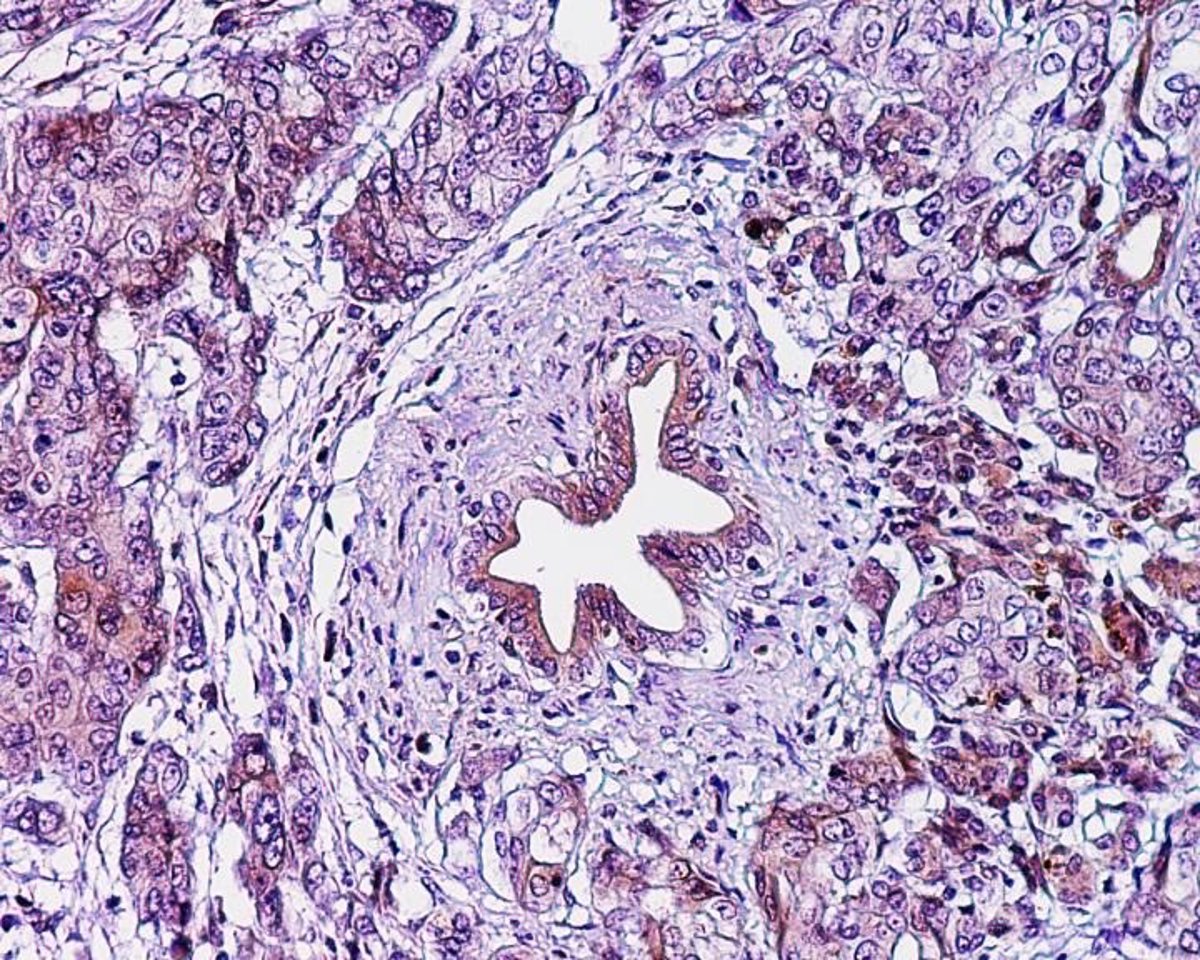

Archivo - Adenocarcinoma ductal pancreático, cáncer páncreas

Archivo - Adenocarcinoma ductal pancreático, cáncer páncreas - EL LABORATORIO DE KEN ZARET, PERELMAN ESCUELA DE M

El cáncer de páncreas se origina en las células pancreáticas y suele diagnosticarse en personas de más de 60 años, con una ligera mayor frecuencia en hombres que en mujeres. Aunque no se encuentra entre los tumores más comunes, sí es uno de los más agresivos, "fundamentalmente porque el diagnóstico suele ser tardío", explica la doctora Ana García García de Paredes, editora asociada de la REED, experta de la SEPD y especialista en aparato digestivo en el Hospital Universitario Ramón y Cajal de Madrid.